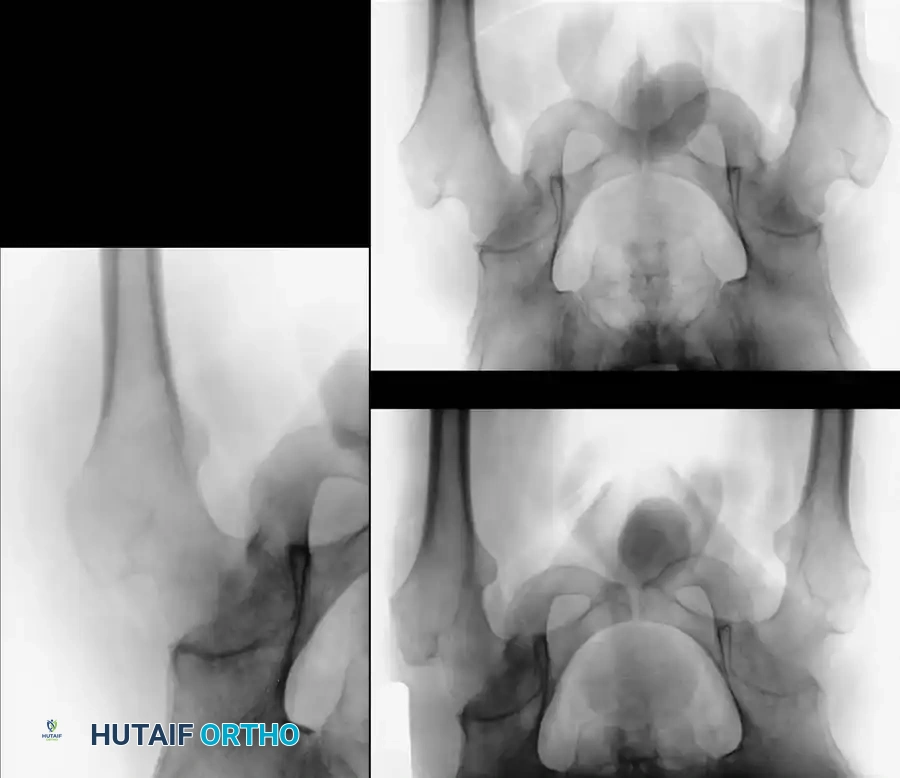

Management of the Neuropathic Hip

Neuropathic arthropathy of the hip presents a profound reconstructive challenge.

Fracture Management:

Fresh femoral neck fractures in neuropathic patients rarely heal after standard internal fixation (e.g., cannulated screws or dynamic hip screws). The true neuropathic nature of the fracture is often unrecognized until the fixation fails, the joint disintegrates, and the hardware cuts out. If internal fixation is attempted, the joint must be strictly immobilized in a hip spica cast postoperatively.

Arthroplasty and Arthrodesis:

* Total Hip Arthroplasty (THA): THA in a neuropathic hip is almost universally contraindicated. The literature is replete with reports of recurrent, intractable dislocations and rapid aseptic loosening.

* Arthrodesis: Achieving a successful arthrodesis of a neuropathic hip is exceptionally rare. Key and Burman historically noted the near impossibility of this procedure.

* Salvage Procedures: When the femoral head and neck have been completely destroyed, a Schanz osteotomy (a valgus-producing proximal femoral osteotomy) may be considered. This procedure medializes the mechanical axis and improves the resting tension of the abductor musculature, providing a stable, albeit stiff, fulcrum for ambulation. Ultimately, surgery of any kind in the neuropathic hip is indicated only for severe, intractable disability.